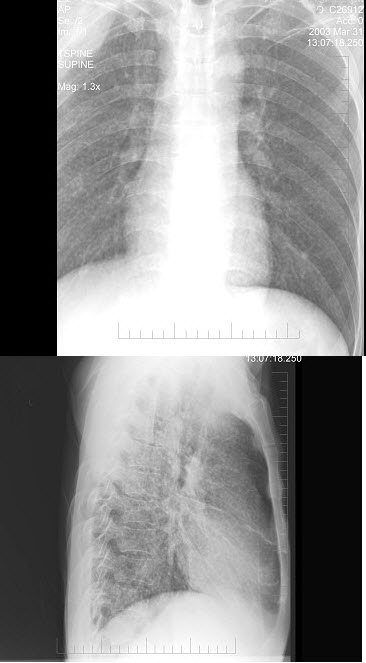

32、单项选择题

男,65岁,胸痛,胸片检查如图,下列诊断中最可能的是()

A.右肺胸膜肥厚

B.右肺不张

C.右侧胸腔积液

D.右肺炎症

E.以上都不对